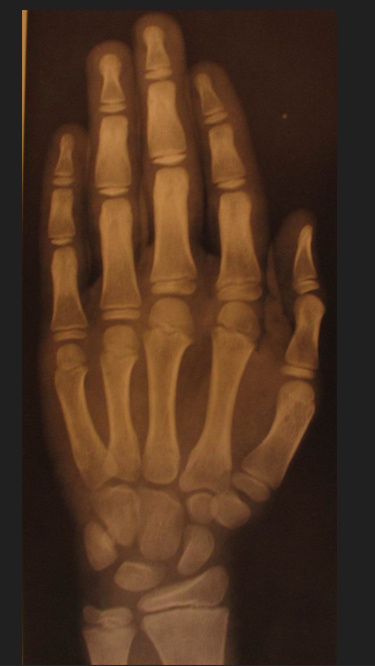

Для определения костного возраста выполняют рентгенографию кистей рук с лучезапястными суставами. Далее проводят оценку костного возраста согласно одной из систем (Greulich and Pyle, The Tanner–Whitehouse Method и другие).

Пример определения костного возраста по методике Greulich and Pyle.

Мальчик, костный возраст 11 лет.